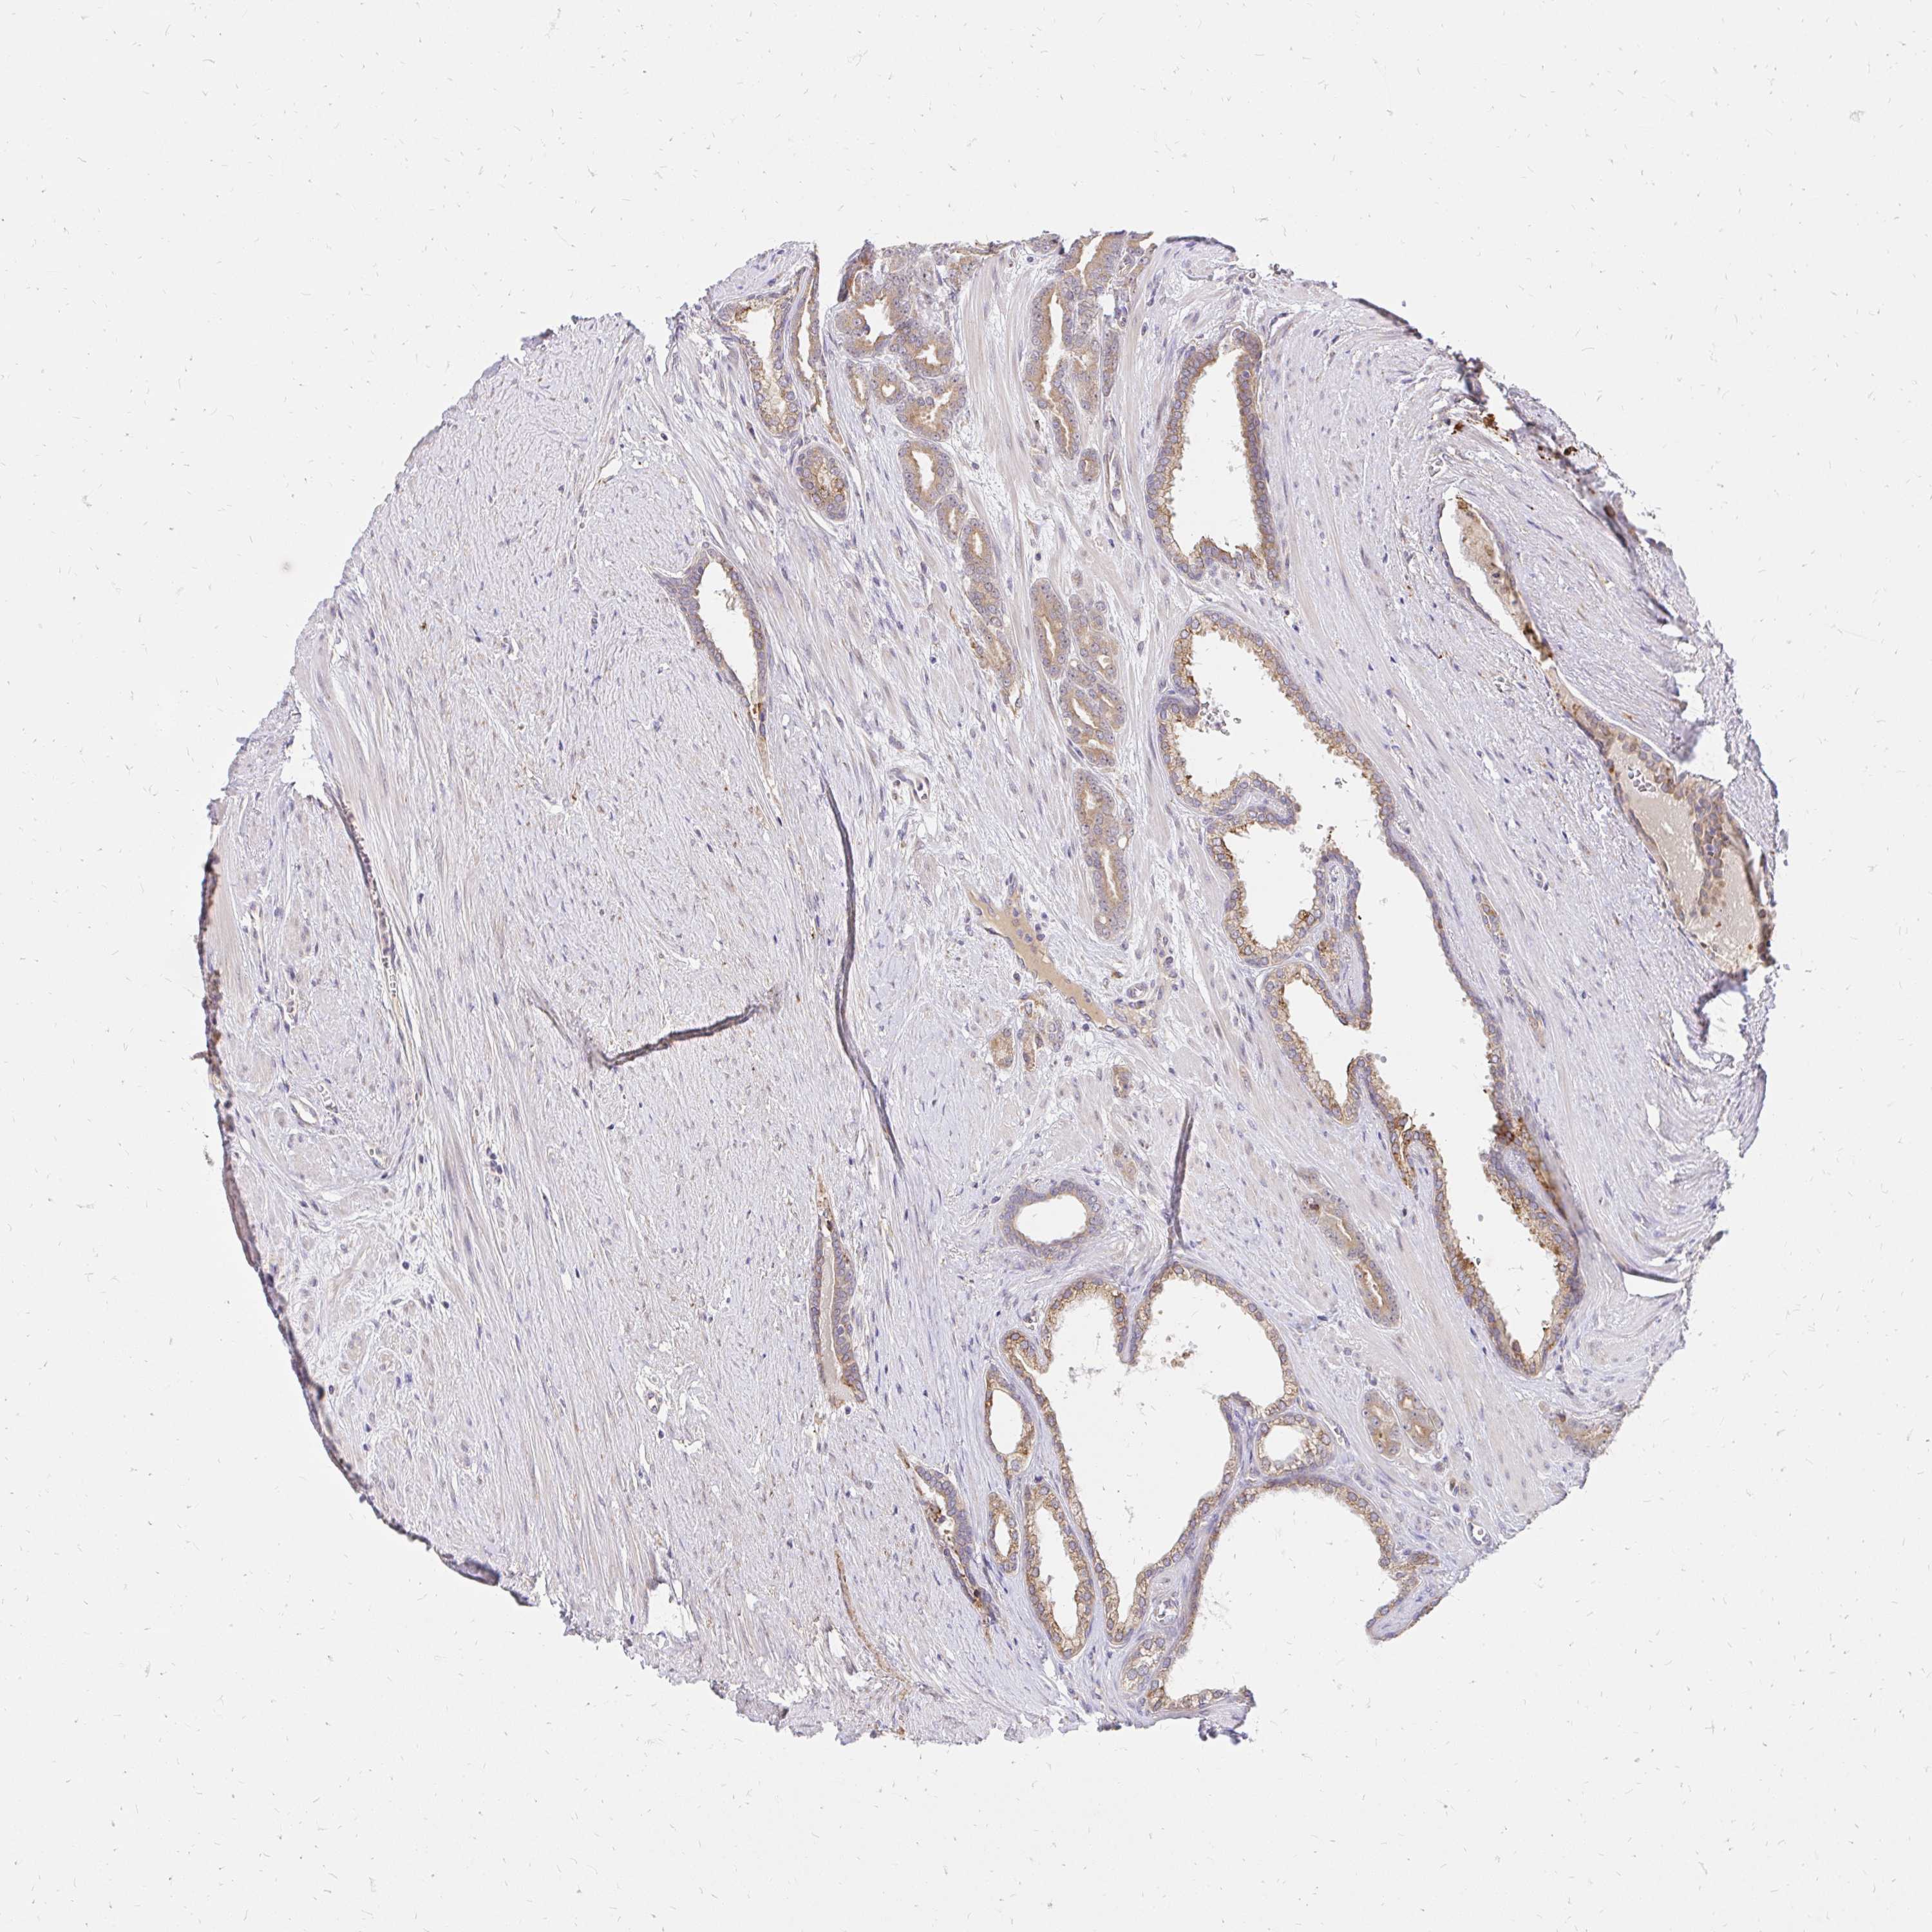

PROSTATE CANCER - Protein expressioni

A mouse-over function shows sample information and annotation data. Click on an image to view it in a full screen mode. Samples can be filtered based on level of antibody staining by selecting one or several of the following categories: high, medium, low and not detected. The assay and annotation is described here.

Antibody stainingi

Antibody staining in the annotated cell types in the current human tissue is reported as not detected, low, medium, or high, based on conventional immunohistochemistry profiling in selected tissues. This score is based on the combination of the staining intensity and fraction of stained cells.

Each image is clickable and will lead to virtual microscopy that enables deeper exploration of all samples and also displays staining intensity scores, fraction scores and subcellular localization as well as patient and tissue information for each sample.

Antibody HPA065419

Adenocarcinoma, High grade

Adenocarcinoma, NOS

Adenocarcinoma, Low grade